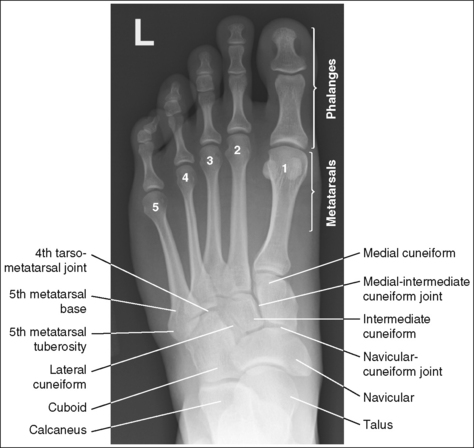

Foot: Anteroposterior Axial Projection (Dorsoplantar),

The foot demonstrates an AP projection. The joint space between the medial (first) and intermediate (second) cuneiforms is open, approximately 0.75 inch (2 cm) of the calcaneus is demonstrated without talar superimposition, and concavity on both sides of the first metatarsal midshaft is equal.

The third metatarsal base is at the center of the exposure field. The proximal calcaneus, talar neck, tarsals, metatarsals, phalanges, and surrounding foot soft tissue are included within the collimated field.